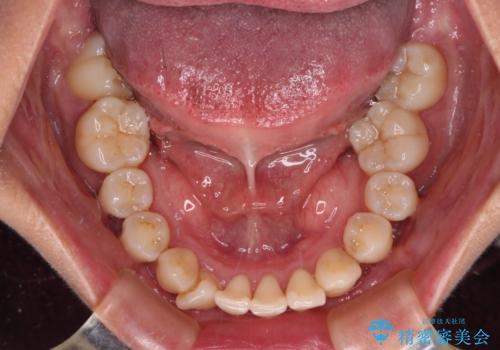

【モニター】上顎前突と奥歯の鋏状咬合 補助装置を用いたインビザライン矯正治療

- 前歯の歯列不正と奥歯の咬みにくさを気にして来院された患者様です。

インビザラインでの矯正治療を希望されていましたが、奥歯の咬み合わせがインビザライン単独では改善困難と判断されたので、補助装置を併用することとしました。

上顎最後臼歯は極端に外側を向いており、下顎骨に対して上顎骨が前方に位置していたため、補助装置により最後臼歯を一気に内側に引き込むとともに、上顎臼歯を後方移動させ、奥歯の咬み合わせが改善した後に、上下インビザラインにより歯列全体を整えていくこととしました。

奥歯の咬み合わせを事前に望ましい位置に改善したことで、インビザライン単独では改善が最も困難な状況を排除することができ、非常に理想的な仕上がりとなりました。